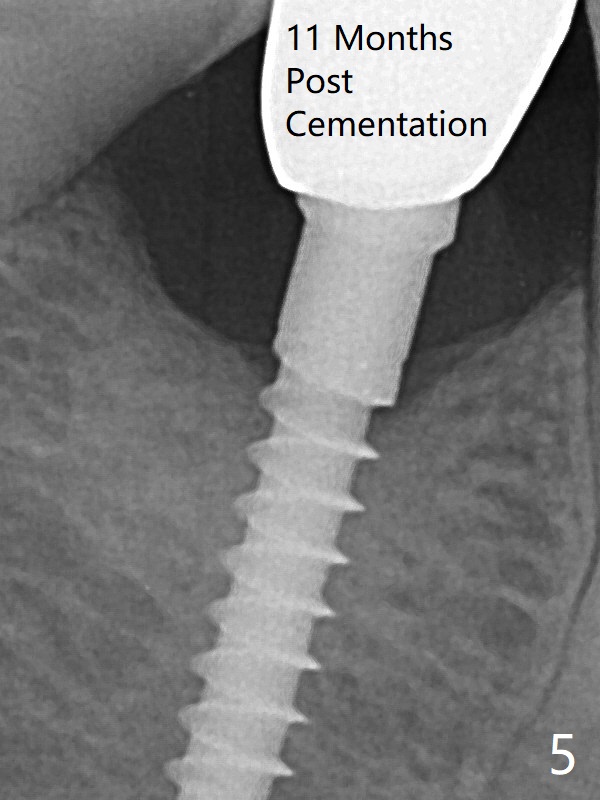

The mesial surface of the tooth #31 is reduced prior to osteotomy (Fig.1 >) so that the mesiodistal width of the edentulous area is 4.5 mm. An incision is made instead of tissue punch because of the narrow keratinized gingiva. The potential osteotomy site happens to have nonkeratinized tissue. Because of apparently sufficient clearance from the Inferior Alveolar Canal (Fig.2 red dashed line), the implant is placed ~ 1 mm deeper later. After suturing, periodontal dressing is applied. At patient's request, a provisional is fabricated with occlusal clearance 26 days postop. The occlusal surface of the provisional perforates 3.5 months postop with the provisional having pressed the gingiva, which is consistent with crestal bone loss (Fig.3). There is minimal bone loss 11 months post cementation; in fact the bone density around the coronal portion of the implant increases (Fig.5). Trajectory PA Last Next Xin Wei, DDS, PhD, MS 1st edition 06/01/2018, last revision 09/18/2019